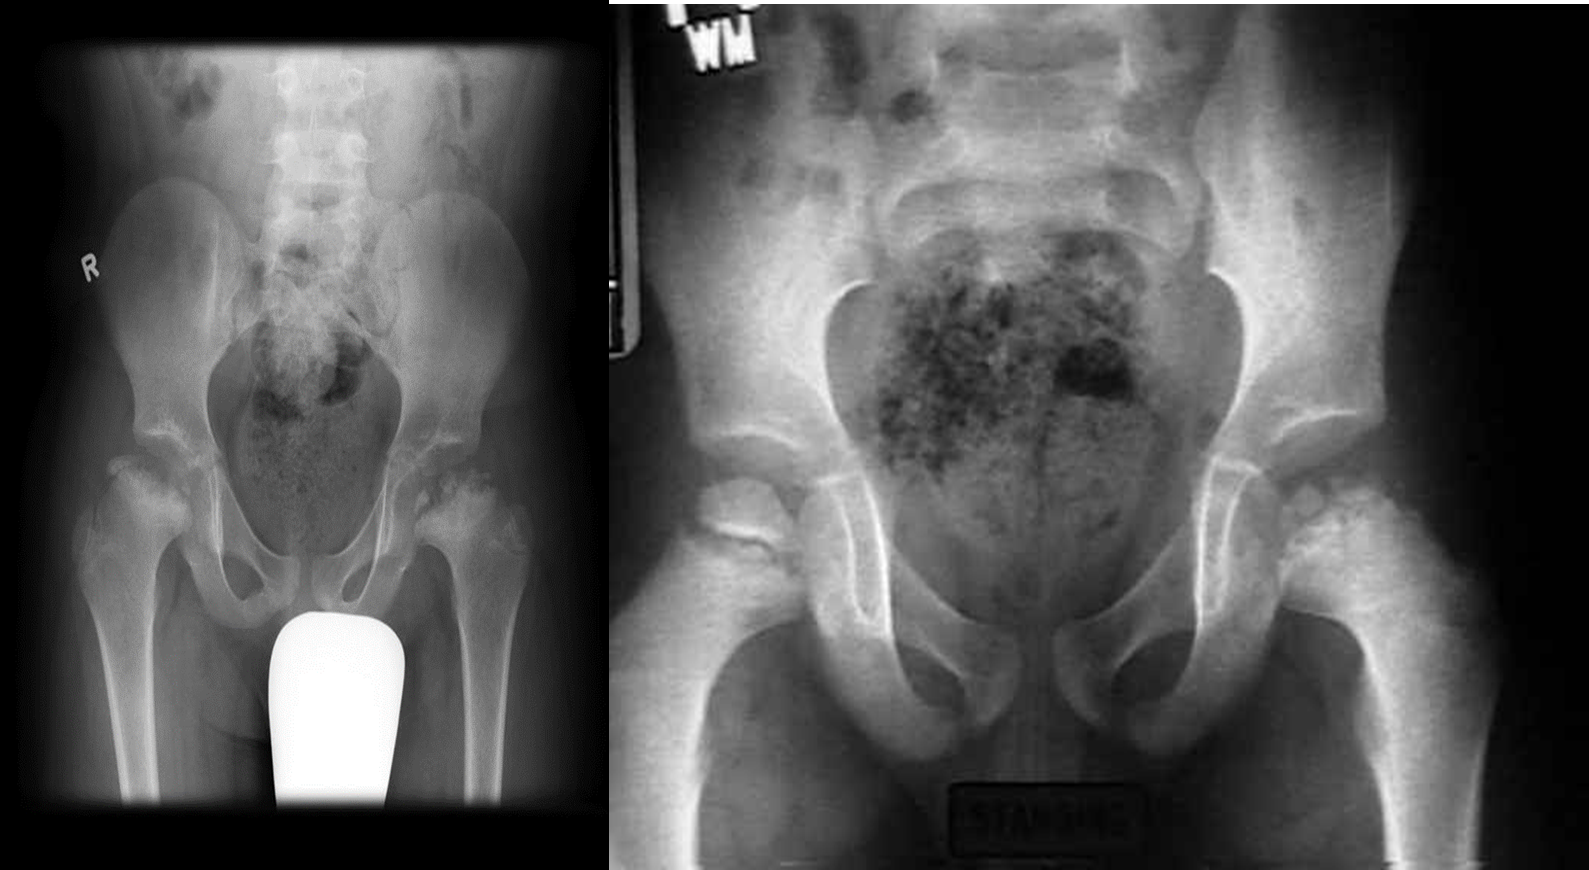

Idiopathic avascular necrosis (Perthes disease) of the growing femoral epiphysis.

It occur in children and more common in boys of 4-8 years. It can be unilateral or bilateral. It present with pain ,with or without limping